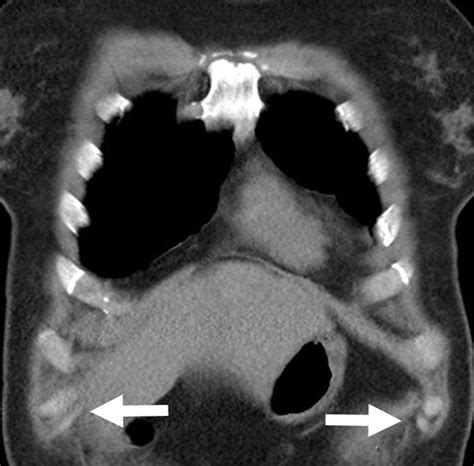

• CT Scans: Computed tomography (CT) scans provide detailed images of the ribcage and can help identify the location and extent of the slipped rib.